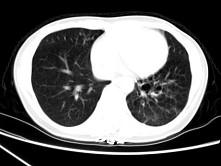

问题 女,30岁,咳痰,咯血,请结合影像图像选择最可能的诊断为 ( )

选项 A、间质性肺炎 B、肺结核 C、支气管扩张并感染 D、支气管囊肿 E、肺部感染

答案 C